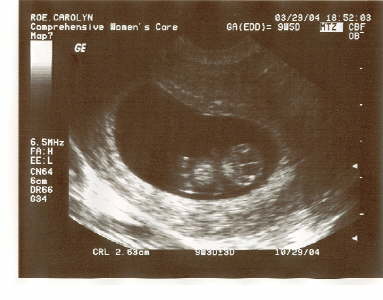

New Baby

Dancing Baby 3